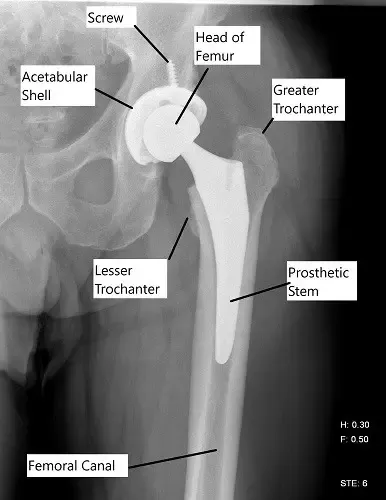

Radiografía que muestra un reemplazo total de cadera.